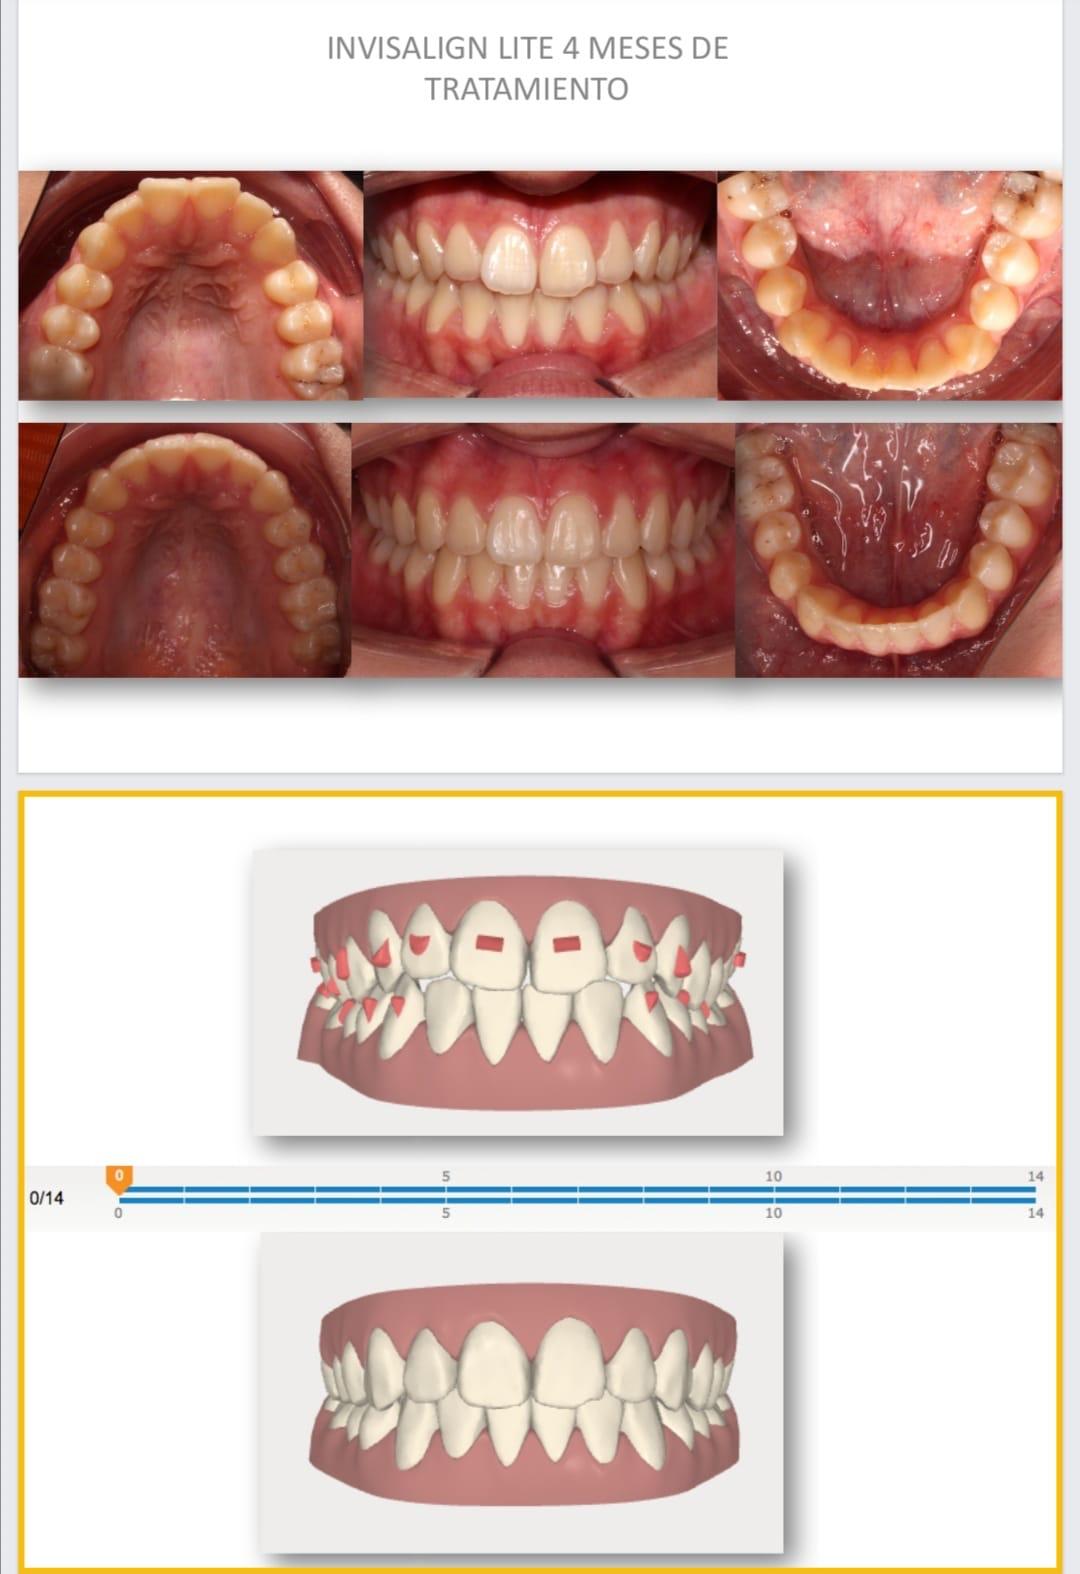

Verás cómo quedará tu sonrisa antes de empezar

Gracias al escáner digital 3D y la simulación, podrás visualizar el resultado de tu tratamiento desde el primer momento.

Casos reales de ortodoncia invisalign

Resultados que transforman sonrisas